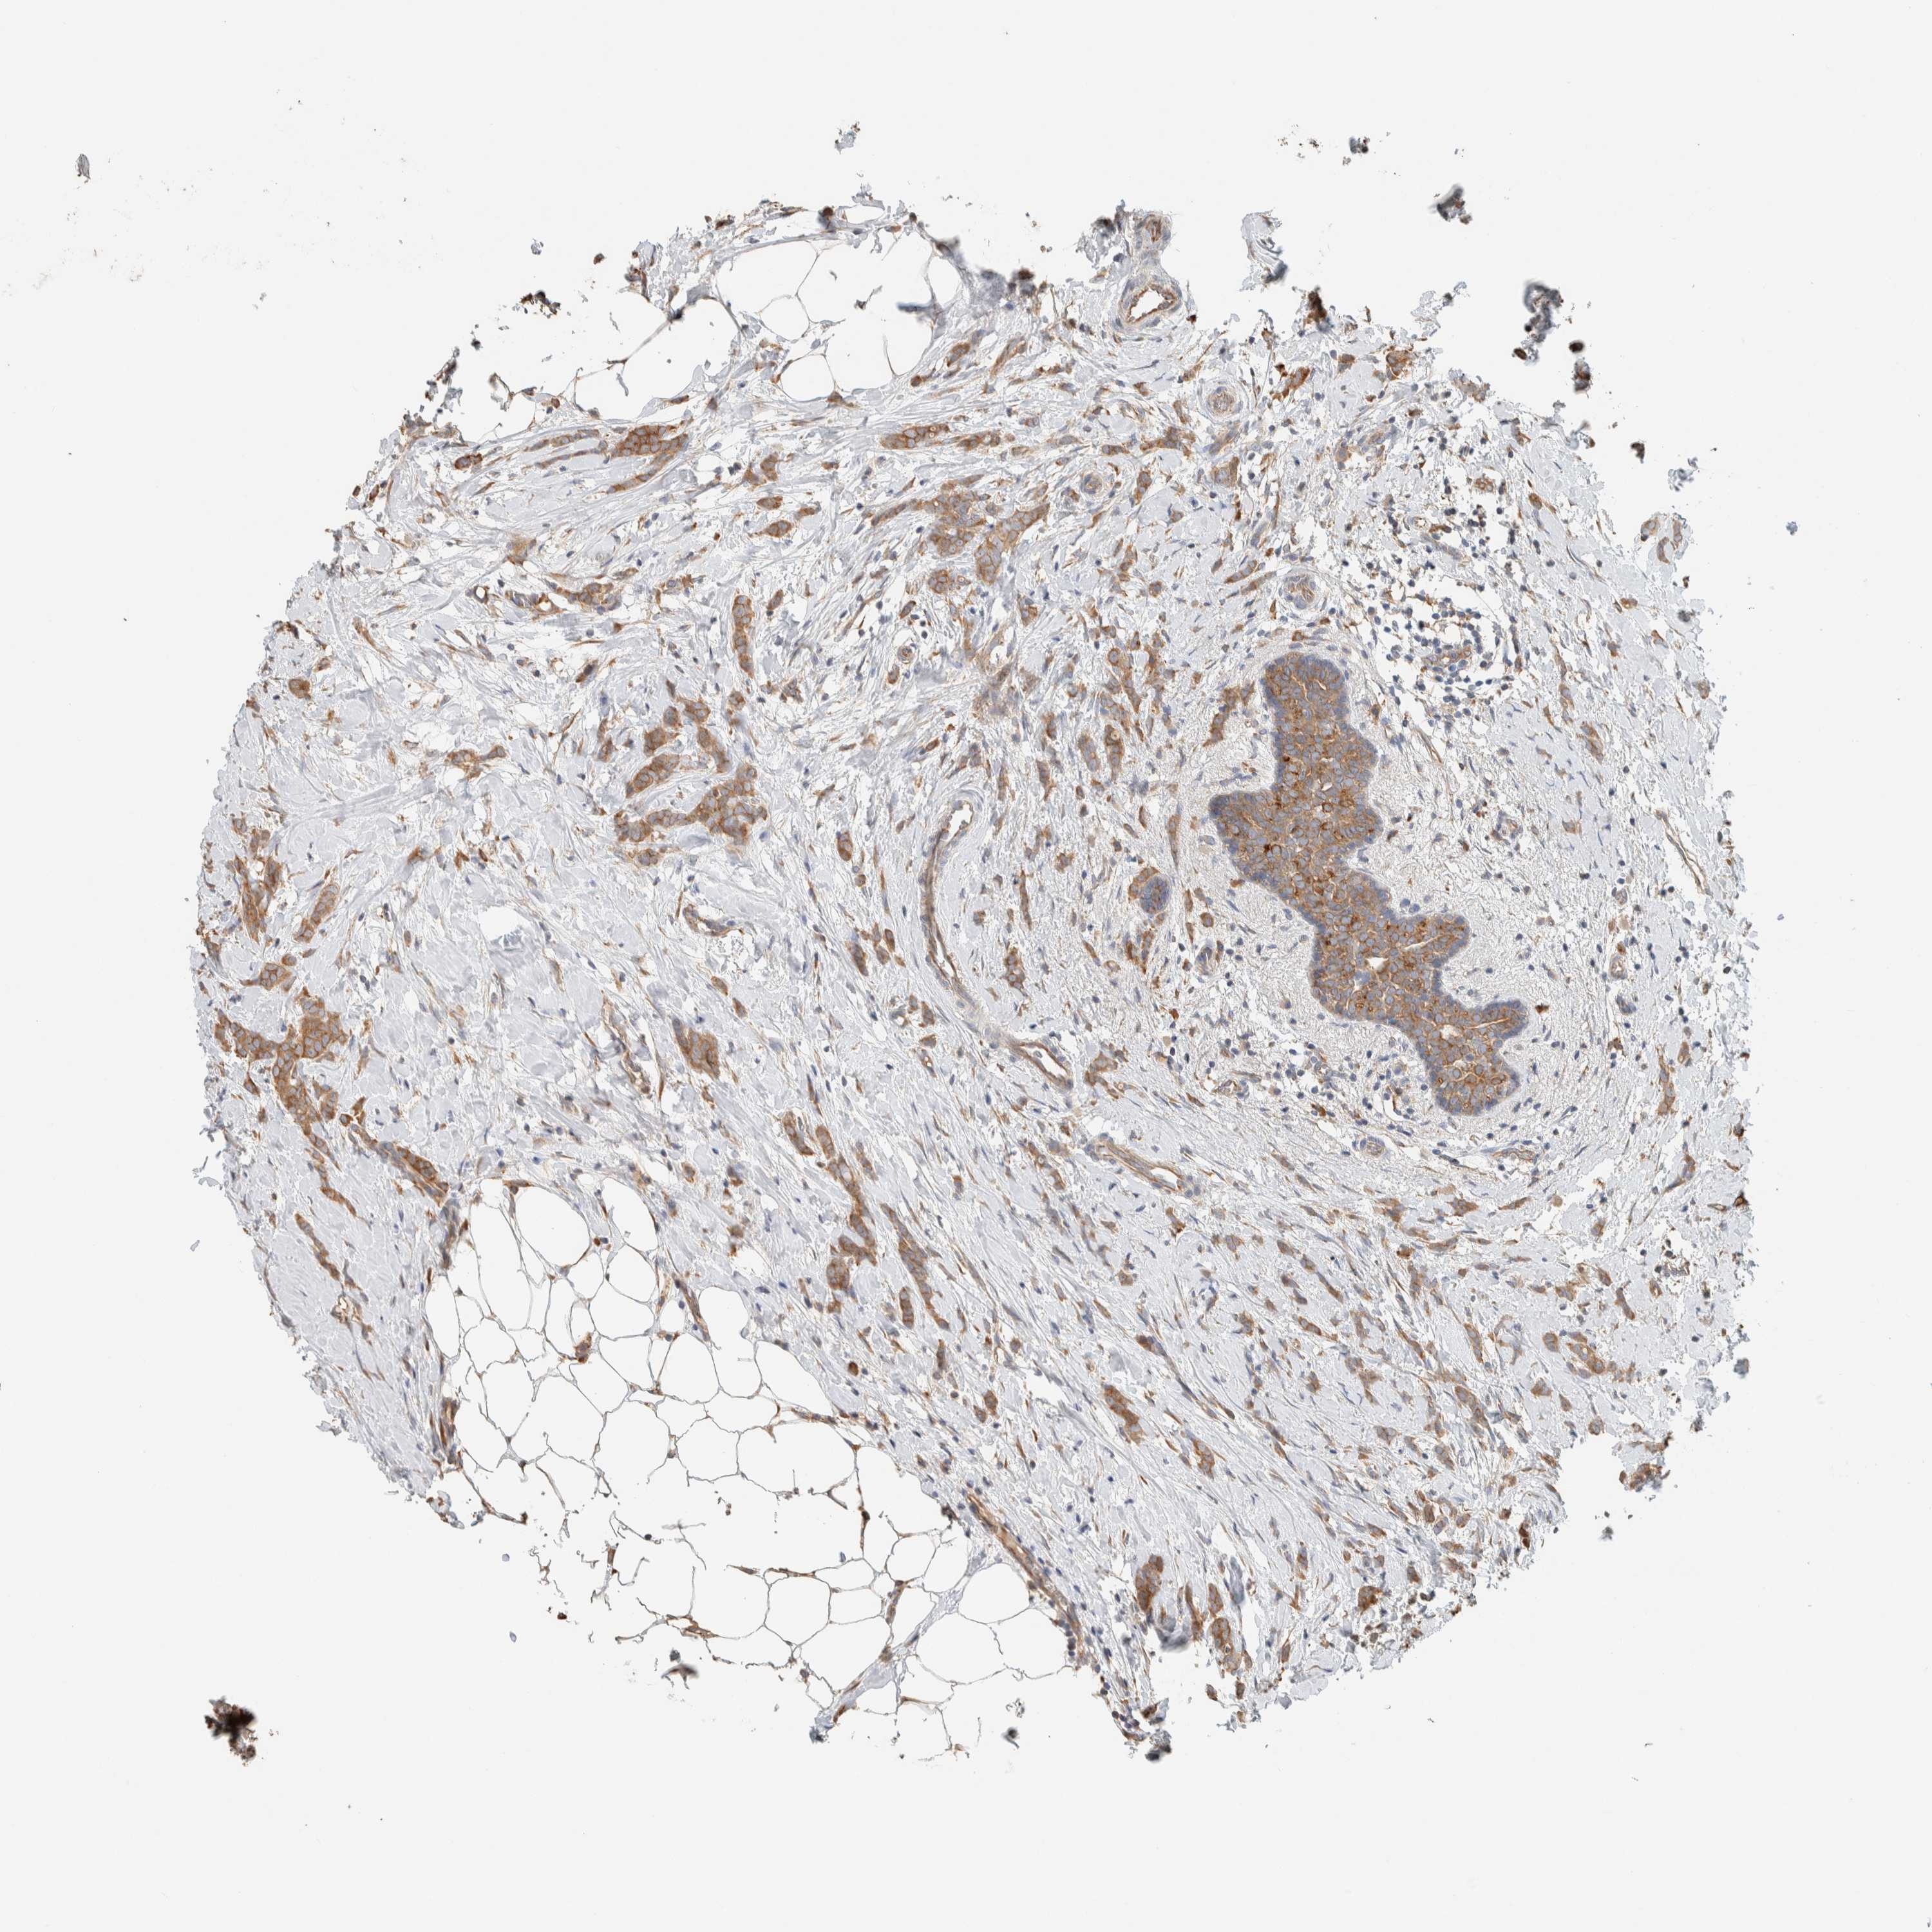

BRCA TCGA BRCA VALIDATION PROTEIN EXPRESSION